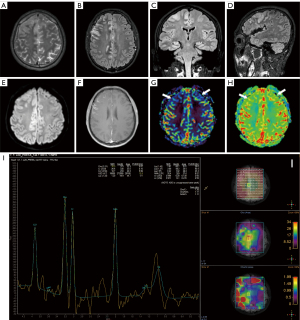

In this group of 11 patients, consisting of 6 males and 5 females, the gender ratio was 6:5. The average age of onset was 32.6±18.6 years, ranging from 14 to 63 years, with a median disease duration of 45 days. All 11 patients underwent brain MRI during the acute stage, with 6 of them (54.5%) showing abnormalities. These were characterized by diffuse and unfixed lesions with point-like or patchy T2 FLAIR hyperintensity in cortical and subcortical regions. Specifically:

- One case showed patchy T2 FLAIR hyperintensity in the left temporal subcortical white matter.

- One case exhibited scattered, patchy-like T2 FLAIR hyperintensity involving both cortical and subcortical regions.

- One case showed T2 FLAIR hyperintensity involving the left frontal and insular lobes (Figure 4A,4B).

- One case had patchy T2 FLAIR hyperintensity involving the right hippocampus and occipito-temporal gyrus.

- One case presented with multiple patchy T2 FLAIR hyperintensities involving the bilateral frontotemporal-parietal areas, thalamus, as well as brainstem (Figure 4C,4D).

- One case had symmetrically distributed patchy T2 FLAIR hyperintensity in the bilateral periventricular region.

Three cases underwent contrast-enhanced scanning: two showed patchy or nodular contrast enhancement within the lesion, while the third did not display pathological contrast enhancement. Two cases underwent MRS scanning, both showing a slightly increased Cho peak, with or without a decreased NAA peak within the lesions.

Among the 11 cases, 4 were re-examined with brain MRI during the convalescent period, all showing reduced lesion areas and decreased T2 FLAIR hyperintensity. The clinical and imaging features of anti-NMDAR encephalitis are detailed in Table 3.

In this group of 5 patients, comprising 4 males and 1 female, the gender ratio was 4:1. The average age of onset was 63.4±9.9 years, ranging from 46 to 69 years, with a median disease duration of 14 days. All 5 patients underwent brain MRI during the acute stage, with 3 (60%) showing abnormalities. Specifically: One case exhibited swelling of the left hippocampus and T2 FLAIR hyperintensity involving the bilateral hippocampi (Figure 5A-5D). The structural brain MRI of 2 patients was normal; however, ASL scanning of one case revealed decreased CBF within the right temporal region (Figure 5E,5F), and 18F-FDG PET-CT of the other revealed decreased FDG metabolism in the right temporal lobe. Thus, imaging abnormalities predominantly involved unilateral or bilateral hippocampus or temporal lobe regions.

Among the 5 cases, three were re-examined with brain MRI during the convalescent period. One case demonstrated improvement in left hippocampal swelling and a reduction in T2 FLAIR hyperintensity in both hippocampi. The other two cases did not undergo ASL and 18F-FDG PET-CT, so no comparison can be made. Table 4 displays the clinical and imaging characteristics of anti-GABABR encephalitis.

MOG antibody cortical encephalitis

In this group of 4 patients, comprising 3 males and 1 female, the gender ratio was 3:1. The average age of onset was 22.8±8.3 years, ranging from 16 to 33 years, with a median disease duration of 23 days. All 4 patients underwent brain MRI during the acute stage, and all (100%) showed abnormalities. Specifically: the frontal lobe was mainly involved in 3 out of 4 cases, one case also involved the temporoparietal lobe, one case also involved the insular lobe. The brain MRI of the 3 patients revealed unilateral (2/3) or bilateral (1/3) cortical swelling, with T1WI hypointensity, T2 FLAIR hyperintensity, DWI normal (1/3) or mild hyperintensity (2/3). While the other patient showed atrophy of the right hippocampus with T2 FLAIR hyperintensity. One patient underwent MRS scanning, showing decreased NAA peak and increased Cho peak. ASL scanning in two patients revealed decreased CBF within the cortical lesions. Contrast-enhanced scanning was performed on four patients: two showed contrast enhancement in the lesioned cortex and adjacent meninges, while two showed no pathological contrast enhancement (Figure 6).

Three out of the four patients were re-examined with brain MRI during the convalescent period. The MRI abnormalities in these three cases significantly improved or disappeared after immunotherapy, while one patient was lost to follow up. Table 5 presents the clinical and imaging characteristics of MOG antibody cortical encephalitis.

Anti-NMDAR encephalitis is the most common type of AE, with 66% showing normal brain MRI. MRI abnormalities, when present, vary widely in location and degree, often manifesting as T2 FLAIR hyperintensity in the medial temporal lobe, sub-cortical white matter, periventricular regions, and cortical and leptomeningeal enhancement (26). Given the lack of specificity in structural brain MRI, functional imaging techniques have gained attention. Studies (27,28) have shown that medial occipital hypometabolism on 18F-FDG PET-CT could serve as an early biomarker for anti-NMDAR encephalitis, often co-existing with frontotemporal hypermetabolism and normalizing after immunotherapy. ASL, a sensitive technique for evaluating regional CBF without contrast agents, can detect hyperperfusion consistent with areas affected by acute or subacute inflammation (29-31).

In this study, 54.5% (6/11) exhibited abnormal brain MRI, with diffuse and unfixed lesions manifesting as point-like or patchy T2 FLAIR hyperintensity in cortical and subcortical regions, consistent with previous studies (14,26,27). Additionally, two out of three cases who underwent contrast enhanced scanning showed enhancement within the lesions. MRS in two cases revealed a mild increase in Cho peaks within the lesions, with or without decreased NAA peaks. These results highlight the advantages of multi-modal MRI in diagnosing anti-NMDAR encephalitis.

Anti-GABABR encephalitis is often characterized by limbic encephalitis (6). Nearly one-third exhibited abnormal brain MRI, typically presenting as T2 FLAIR hyperintensity in the medial temporal lobe and hippocampus, with occasional cortical involvement (32). The volume and signal intensity of the hippocampus may change as the disease progresses, resulting in hippocampal sclerosis during follow-up (6,32,33). As shown by previous studies, 18F-FDG PET-CT underwent during the acute phase showed medial temporal lobe hypermetabolism and cortical hypometabolism, the latter may be caused by synaptic dysfunction, while the former may be related to epileptic focus activity rather than inflammatory response (34,35).

In the present study, 60% of patients diagnosed with anti-GABABR encephalitis exhibited imaging abnormalities, including T2 FLAIR hyperintensity in the bilateral hippocampi. Among the two cases with normal structural brain MRI, one showed decreased CBF in the right temporal region on ASL, the other displayed FDG hypometabolism in right temporal lobe on 18F-FDG PET-CT, which was inconsistent with previous studies and may be related to the course and severity of disease and the phase of seizure. These findings suggested that functional imaging techniques such as 18F-FDG PET-CT and ASL may be helpful for diagnosis of anti-GABABR encephalitis.

Cortical FLAIR-hyperintense lesions in anti-MOG-associated encephalitis with seizures (FLAMES) (7) is a special phenotype of MOGAD that was first described in 2017 (36), manifesting as headache, fever, seizures, cortical symptoms, unilateral or bilateral cortical swelling and T2 FLAIR hyperintensity on brain MRI. Reviewed by Budhram et al. (7), 20% of patients reported bilateral cortical involvement, with the most common locations being the frontal, temporal, and parietal lobes, excluding white matter involvement; 30% of patients exhibited adjacent sulcal T2 FLAIR hyperintensity and/or post-contrast leptomeningeal enhancement.

In this study, three out of four cases showed unilateral or bilateral cortical swelling, with the frontal lobe mainly involved, with T2 FLAIR hyperintensity, with or without diffusion restriction, which are consistent with previous studies (7,36). As shown by Shirozu et al.’s study (37), during the ictal phase, the epileptogenic cortex was in an extreme electrophysiological state with increased consumption of glucose and oxygen, leading to compensatory regional hyperperfusion, which may result in energy deficit of the Na+/K+-ATPase pump, causing cytotoxic edema, which in turn lead to DWI restriction and reduced ADC (31), but usually mild and reversible (38). Thus, the findings of DWI depended on the degree and duration of epileptic activities during the ictal phase. Therefore, the different results of DWI in our study may be related to the different time points of MRI acquisition, the severity of the disease and the frequency of seizures. Additionally, two cases revealed decreased CBF in the lesioned cortex on ASL. This was different from previous studies which showed increased perfusion and vascularity, and may be due to different time points of MRI acquisition. In the near future, we will increase the sample number and conduct dynamic observation to further clarify the alterations of cerebral perfusion.